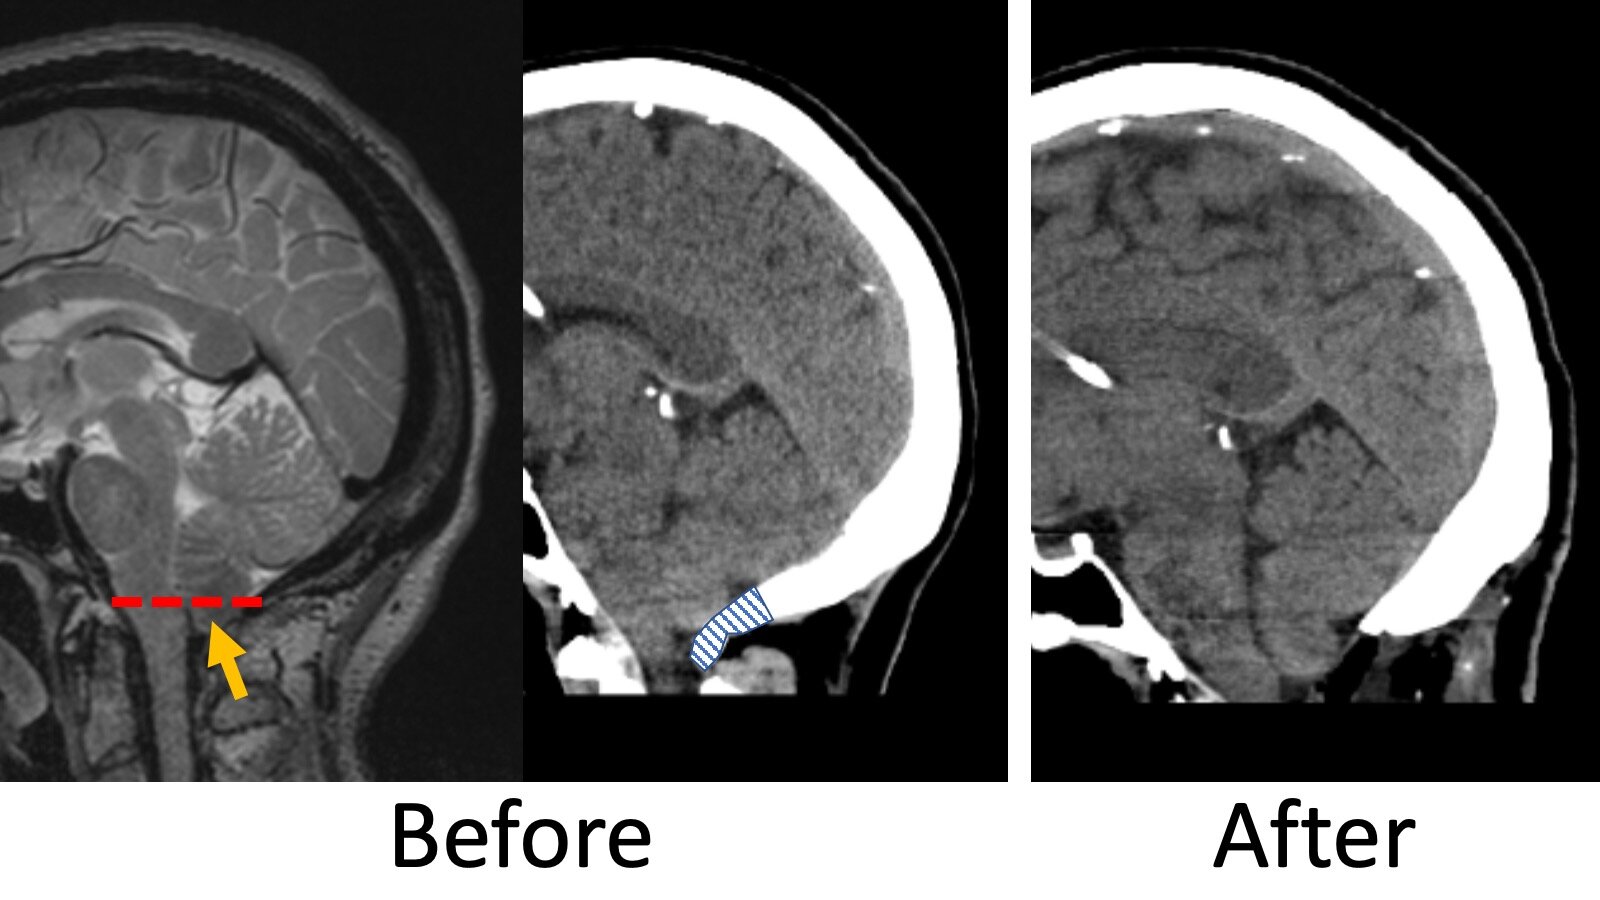

Illustrative cases of MRI imaging courses after bony for Pain Management After Chiari Decompression Surgery When you pick up your medication, your pharmacist will discuss any further precautions or restrictions. My third week i would feel good one day then bad the next day. I was in lots of pain, exhausted and had no appetite. There are variations in the anatomical changes that may lead to chiari malformation resulting in a relatively small. It is. Pain Management After Chiari Decompression Surgery.